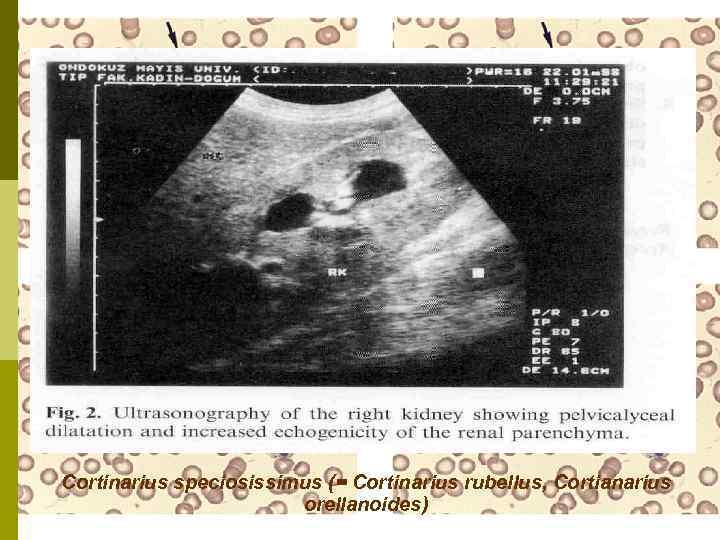

Нефропатия, вызванная «волшебными грибочками» Отравление грибами Cortinarius speciosissimus (= Cortinarius rubellus, Cortianarius orellanoides) приводит к ОПН, которая необратима более чем у половины больных. Такие случаи зарегистрированы в Польше, Финляндии, Шотландии, Швеции, Норвегии, Франции. Вне Европы – в Канаде. Морфология: почки увеличены в размере, клубочки не изменены, выраженный интерстициальный отек, канальцы заполнены белковым содержимым, иммунофлуоресценция отрицательна.

Cortinarius speciosissimus (= Cortinarius rubellus, Cortianarius orellanoides)